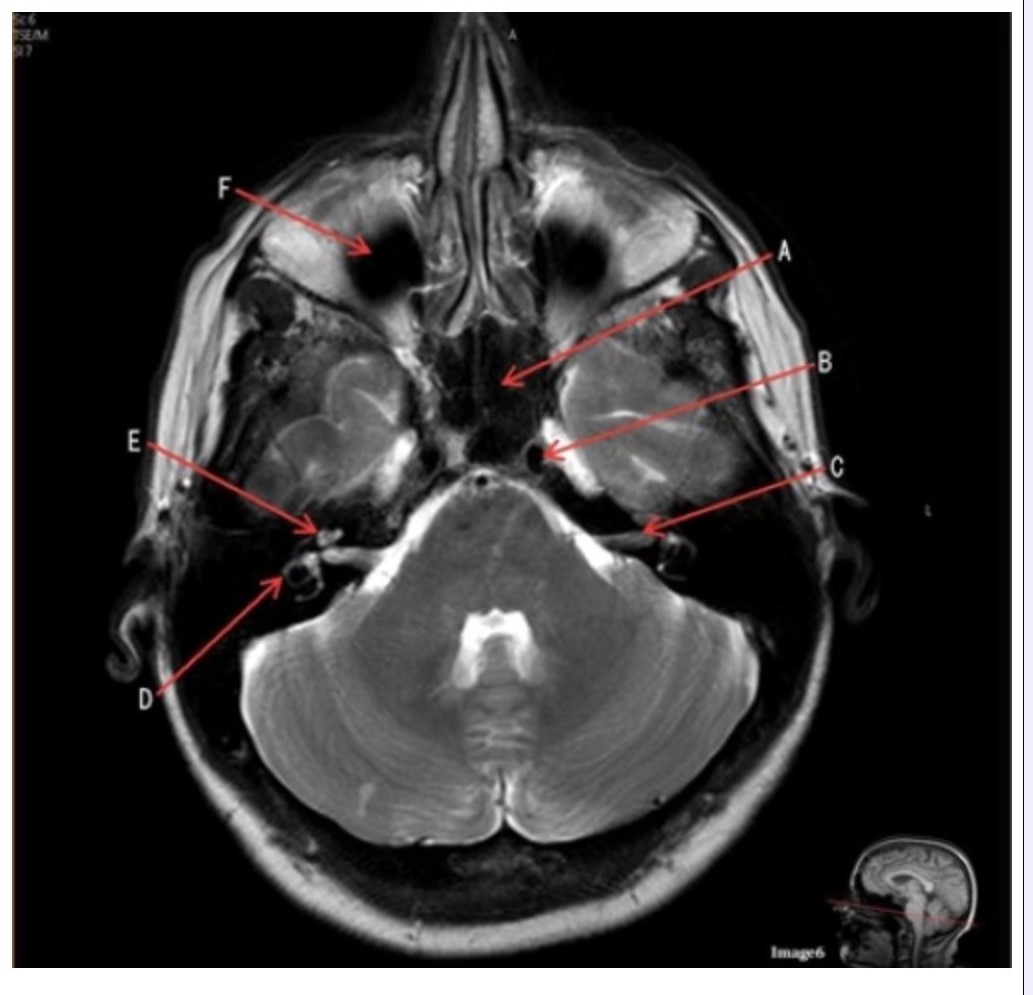

Letter A in Image 6 is pointing to:

A. Maxillary sinus

B. Sphenoid sinus

C. Frontal sinus

D. Internal carotid artery

Letter C in Image 6 is pointing to:

A. 7th cranial nerve

B. Cochlea

C. Trigeminal nerve

D. Semicircular canal

Letter B in Image 6 is pointing to:

A. Maxillary sinus

B. Sphenoid sinus

C. Vertebral artery

D. Internal carotid artery

Letter F in Image 6 is pointing to:

A. Maxillary sinus

B. Sphenoid sinus

C. Frontal sinus

D. Optic chiasm

Image 6 is an example of a _____ weighted sequence acquired in the _______ imaging plane.

A. T1; Axial

B. T1; Coronal

C. T2; Axial

D. T2; Coronal

E. STIR; Axial

Letter E in Image 6 is pointing to:

A. 7th cranial nerve

B. Cochlea

C. Trigeminal nerve

D. Semicircular canal